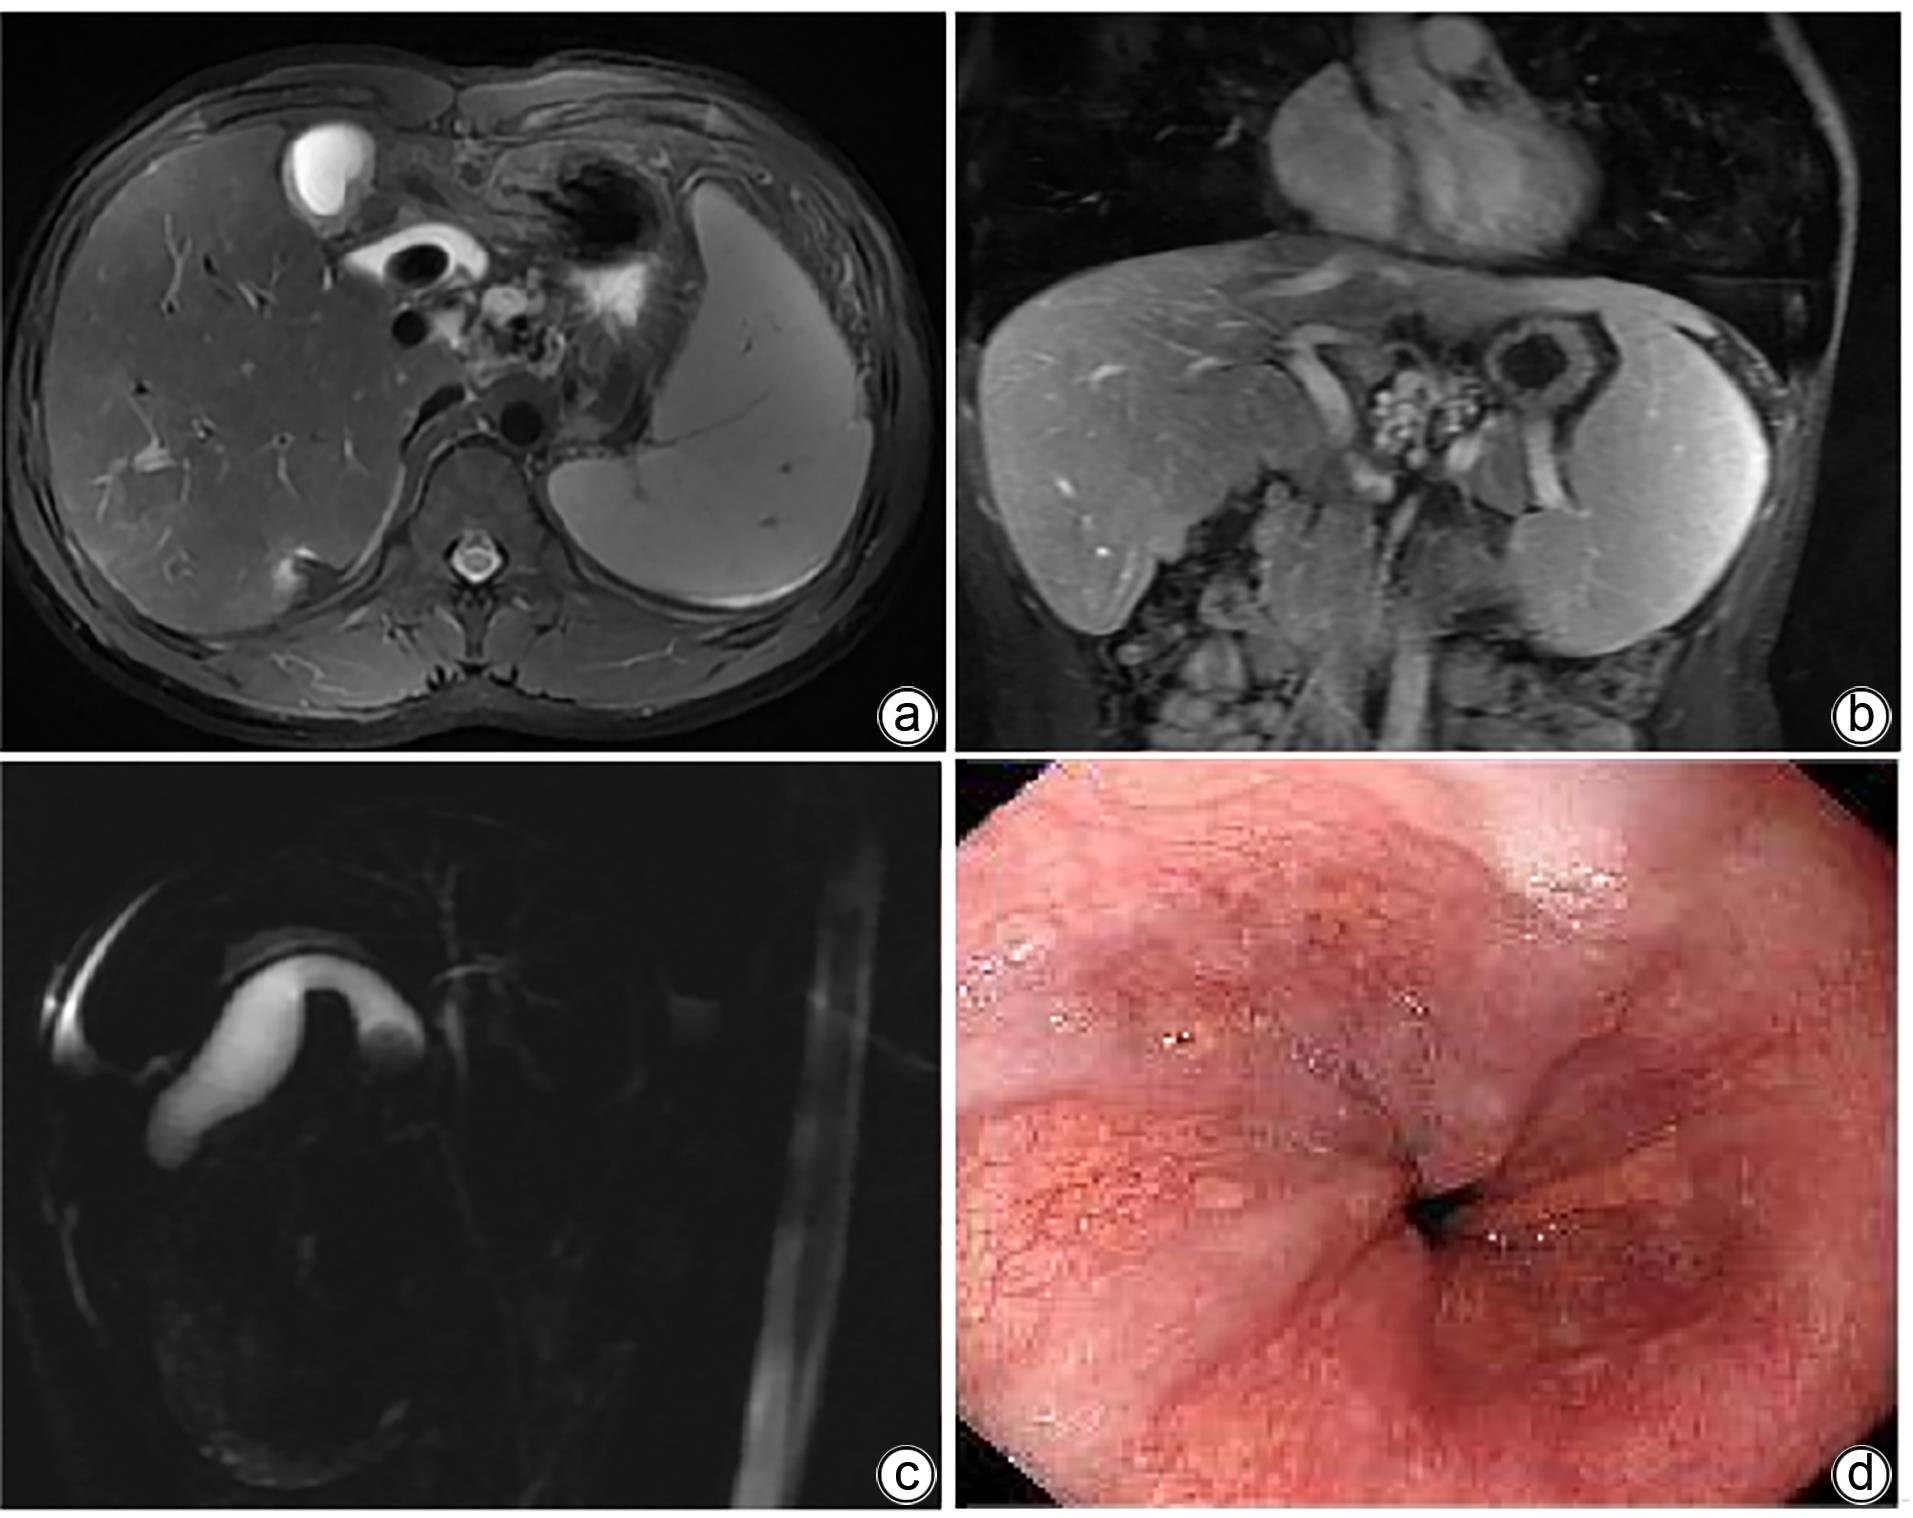

• The disease spectrum of ABCB4 gene mutation involves various diseases such as progressive familial intrahepatic cholestasis type 3 (PFIC3), gallstone disease, intrahepatic cholestasis of pregnancy, portal hypertension, liver cirrhosis, and even primary hepatic and biliary malignancies. A young male patient was admitted to Department of Hepatobiliary Medicine, Eastern Hepatobiliary Surgery Hospital, and was initially diagnosed with liver cirrhosis and gallstones, and he was planned to receive laparoscopic cholecystectomy. Preoperative examination showed abnormal liver function, liver cirrhosis, splenomegaly, and mild esophageal varices, and next-generation sequencing was performed to make a confirmed diagnosis of ABCB4 gene mutation-associated liver cirrhosis with gallstones. The liver function of the patient gradually returned to normal after cholagogic treatment with ursodeoxycholic acid capsules.